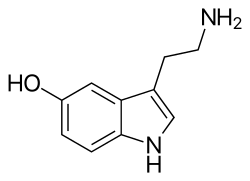

| Serotonin | Animals, plants | 5-OH | H | H | 5-hydroxytryptamine | 50-67-9 |